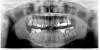

lano Опубликовано 28 сентября, 2011 Поделиться Опубликовано 28 сентября, 2011 Уважаемые специалисты!При перелечивании каналов зуба 17 не удалось пройти один из каналов и удалить из него серебряную проволочку(штифт?), т. к. канал искривлен. Остальные каналы пройдены, поставлена временная пломба. Доктор сказала, что зуб нужно удалять. На вопрос, можно ли сделать резекцию верхушки корня, был ответ: в зубе номер 7 - нельзя, т.к. он очень близко расположен к челюстному суставу. Сейчас зуб болит, пока - терпимо, десна отекла и болит. Что делать, вскрывать десну или удалять зуб?Как долго можно держать временную пломбу?Прошу оценить по снимку, есть ли возможность пройти канал при таком искривлении?Какой прогноз на этот зуб, стоит ли пытаться его спасать? Если да - посоветуйте, каким образом.Действительно ли нельзя делать резекцию в этом случае? Большое спасибо. Ссылка на комментарий

lano Опубликовано 29 сентября, 2011 Автор Поделиться Опубликовано 29 сентября, 2011 (изменено) Спасибо за ответ.Мой доктор работала с микроскопом, извлекла, как она говорит «твердую« часть штифта, а там, где он стал помягче - не смогла. Мне это непонятно, серебро есть серебро, как твердость его может меняться так сильно?А что по снимку видно , кривизна канала не очень сильная, можно его пройти? Изменено 29 сентября, 2011 пользователем lano Ссылка на комментарий

ger_berra Опубликовано 29 сентября, 2011 Поделиться Опубликовано 29 сентября, 2011 Кривизна -понятие достаточно относительное .Рентгеновский снимок-это изображение объёмного предмета на плоскости.Просто глядя на снимок,рассуждать со 100% уверенностью в успехе нельзя. Ссылка на комментарий